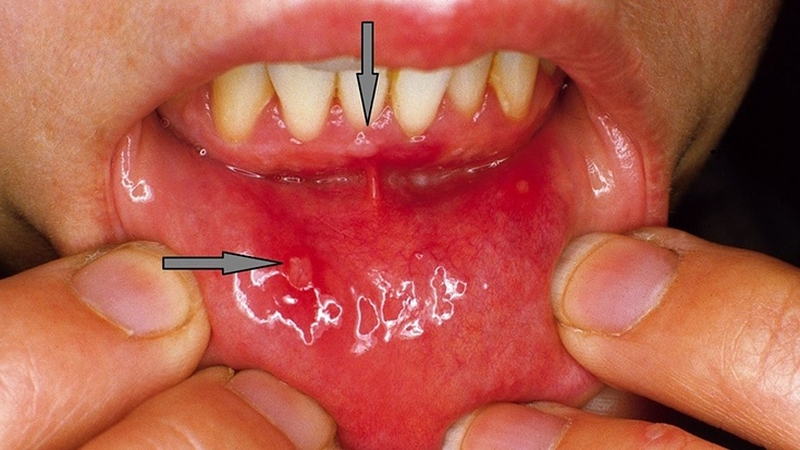

Thời gian 3 - 6 ngày là thời gian ủ bệnh tay chân miệng của người lớn. Sau vài ba ngày các mụn nước nhỏ bắt đầu xuất hiện trong miệng, bàn tay, cánh tay, bàn chân, đùi và mông. Kích thước mụn thường rất nhỏ hoặc như hạt đậu.

Đặc biệt với mụn ở trong miệng hay bị nhầm lẫn là nhiệt miệng nên không để ý chữa trị khiến bệnh càng thêm nặng.